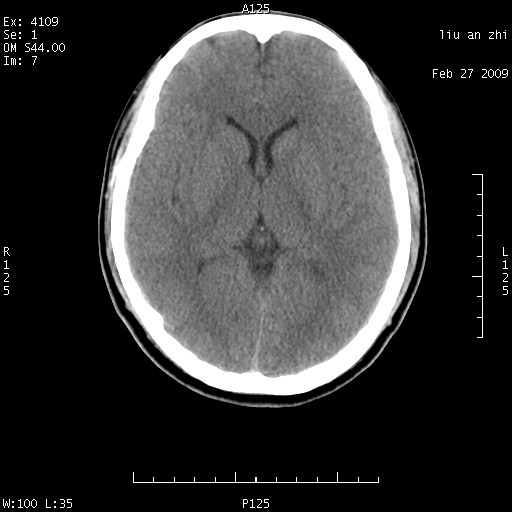

患者:男,32岁 被打伤后3天,自感头昏头痛作头颅ct检查。请大家看一下想什么??

7天后复查头颅ct片:

请注意小脑幕!!!

ct18448的结果:mri检查左侧天幕下血肿

以下是引用深蓝一号在2009-3-9 16:22:00的发言:[br]ct18448的结果:mri检查左侧天幕下血肿。